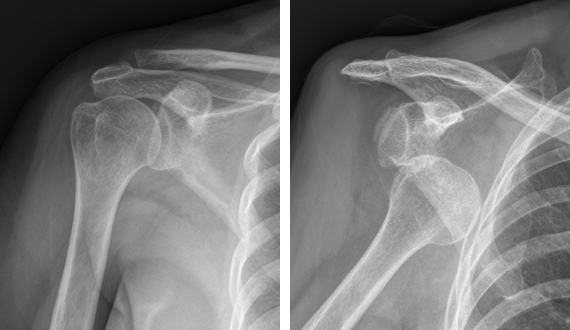

정상어깨(좌) 와 어깨가 탈구된(우) 엑스레이 사진 정상어깨(좌) 와 어깨가 탈구된(우) 엑스레이 사진

급성 탈구인 경우 진찰소견과 엑스레이 소견을 보고 탈구의 방향을 조사하는데 대부분의 경우 팔이 앞쪽으로 빠지는 전방 탈구입니다. 재발성 탈구가 되면 MRI 등으로 관절순 또는 인대들의 상태를 분석하는 것이 필요합니다. 또한 재발성 탈구시 골절을 동반하는 경우와 골결손이 심하면 수술전 CT사진이 필요합니다.